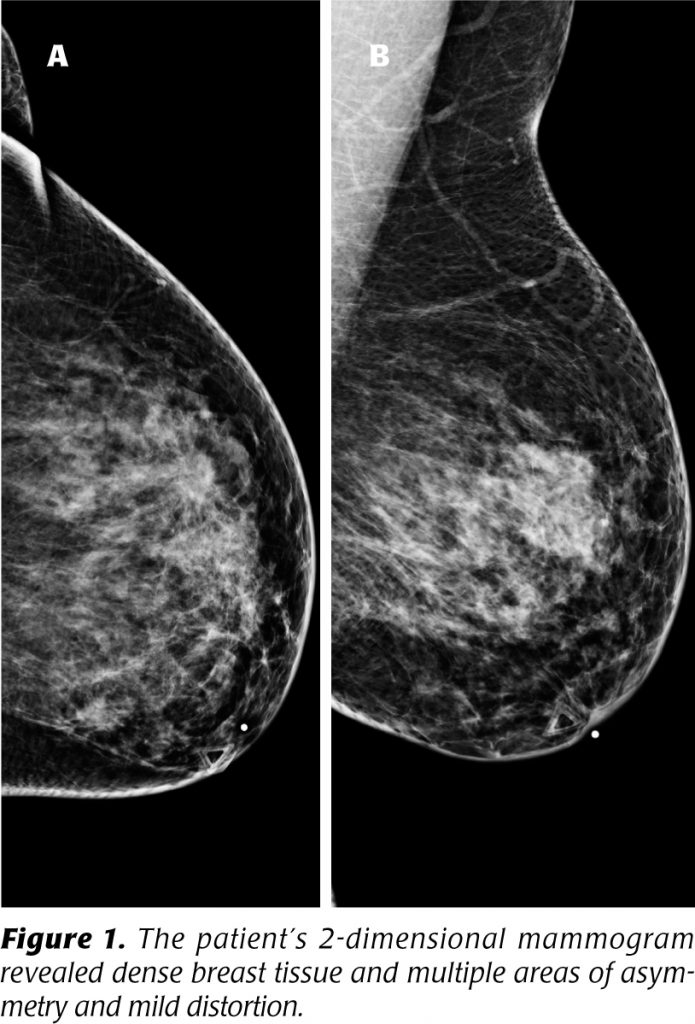

Tomosynthesis, Definitive image for improved breast cancer diagnosis Pain Under My Left Breast Cancer Should breast pain cause me to be concerned about breast cancer? Here are the potential causes and when to see a doctor,. While it’s good to be vigilant and cautious when it comes to breast symptoms, the good news is that breast pain is very common. This includes conditions such as a clogged milk duct, mastitis, and a breast. What. Pain Under My Left Breast Cancer.